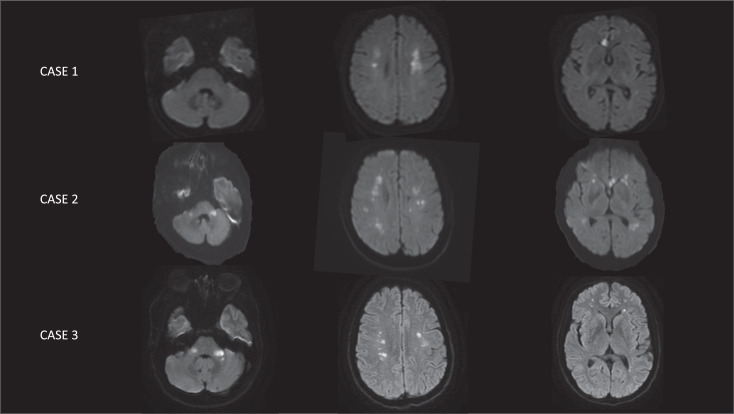

Results: In our 3 patients, aged 40-58 years, stroke symptoms occurred one to 11 days after the first COVID-19 manifestations. Pulmonary symptoms were mild or absent. One patient presented with hemodynamic failure presumably related to acute cardiomyopathy. Brain magnetic resonance imaging revealed in all cases, ischemic lesions within border-zone areas in both cerebral hemispheres, lesions in the genu of the corpus callosum or in the medium cerebellar peduncles in two cases. The watershed pattern of ischemic lesions was detected in two cases despite any blood pressure drop or severe respiratory dysfunction. Seven CADASIL patients presenting with acute brain infarcts (multiple in 4/7) in context of SARS-CoV-2 infection were identified in literature, despite no fall in blood pressure except for one of them.

Abstract Image